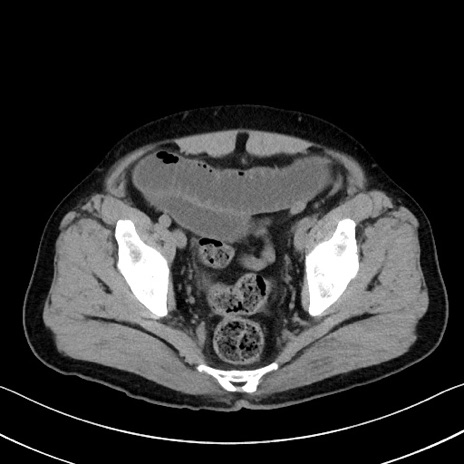

症例35(横断像)

【症例】70歳代 男性

【主訴】腹部膨満、嘔吐

【現病歴】昨日より腹部膨満感出現。本日増悪し、仙痛出現。嘔吐あり、受診。

【既往歴】糖尿病、胆摘後

【身体所見】BP 149/80mmHg、HR 74/min、BT 35.9℃、腹部:膨満、軟、圧痛なし。腸雑音減弱あり。上腹部正中切開瘢痕あり。

【データ】WBC 13500、CRP 1.72